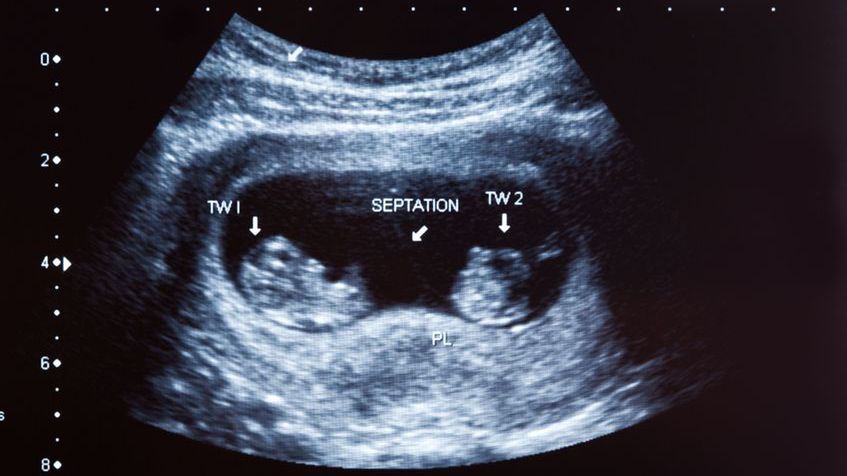

W każdym z tych przypadków mamy do czynienia z tak zwanym bliźniakiem pasożytniczym - swoistą formą bliźniaka syjamskego. W przypadku bliźniąt syjamskich, dochodzi do zaburzeń genetycznych i nieprawidłowego podziału komórek na wczesnym etapie ciąży mnogiej. Jeśli owy podział jest symetryczny, każdy z płodów – choć są ze sobą złączone i miewają wspólne narządy – rozwja się równocześnie.

Jeśli natomiast do podziału komórek dojdzie niesymetrycznie, jeden z bliźniaków w końcu przestanie się rozwijać, a drugi będzie rósł. Mniejszy stanie się w końcu od większego zależny i żył będzie tylko i wyłącznie dzięki niemu. Dlatego nazywa się go "bliźniakiem pasożytniczym".

Naukowo rzecz ujmując, fetus in fetu jest postacią monozygotycznej ciąży wielopłodowej. Jak podają specjaliści, powstaje w wyniku nierównomiernego podziału komórek, które ulegają swoistemu wchłonięciu do organizmu bardziej rozwiniętego płodu.